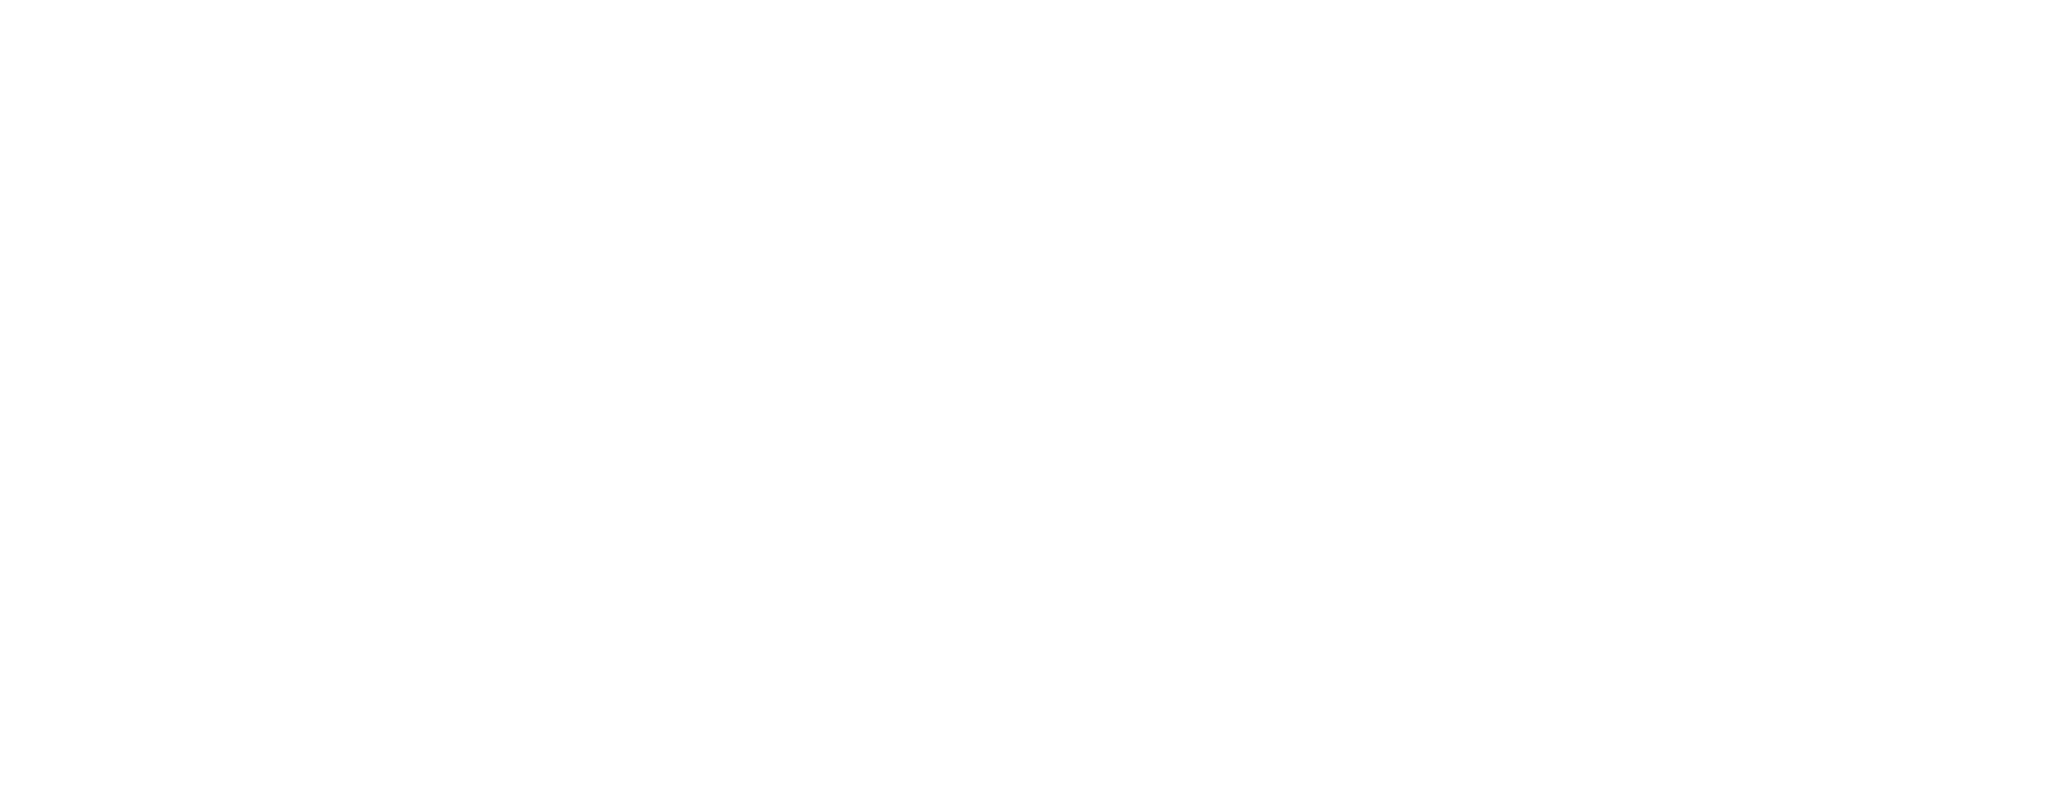

Gli impianti dentali All-on-4 / All-on-6 rappresentano una soluzione innovativa per chi soffre di una perdita multipla dei denti. A differenza delle protesi rimovibili tradizionali, offrono maggiore stabilità, comfort Q praticità.

La procedura prevede il fissaggio di una protesi fissa su radici dentali artificiali ancorate saldamente all’osso mascellare. Il risultato è una soluzione

affidabile, funzionale e duratura, ideale per ripristinare il sorriso e la qualità della vita.

La mancanza di denti, se non trattata, può causare problemi funzionali come difficoltà nella masticazione e riassorbimento dell’osso mascellare. Le tecniche All-on-4 e All-on-6 rappresentano una soluzione efficace sia per la perdita parziale che totale dei denti. Ancorando radici dentali artificiali in modo stabile all’osso e applicando protesi fisse dall’aspetto naturale, è possibile ripristinare estetica e funzionalità. Il numero di impianti necessari viene definito in base alla struttura ossea e al grado di perdita dentale, garantendo un sorriso confortevole stabile e dall’aspetto naturale.